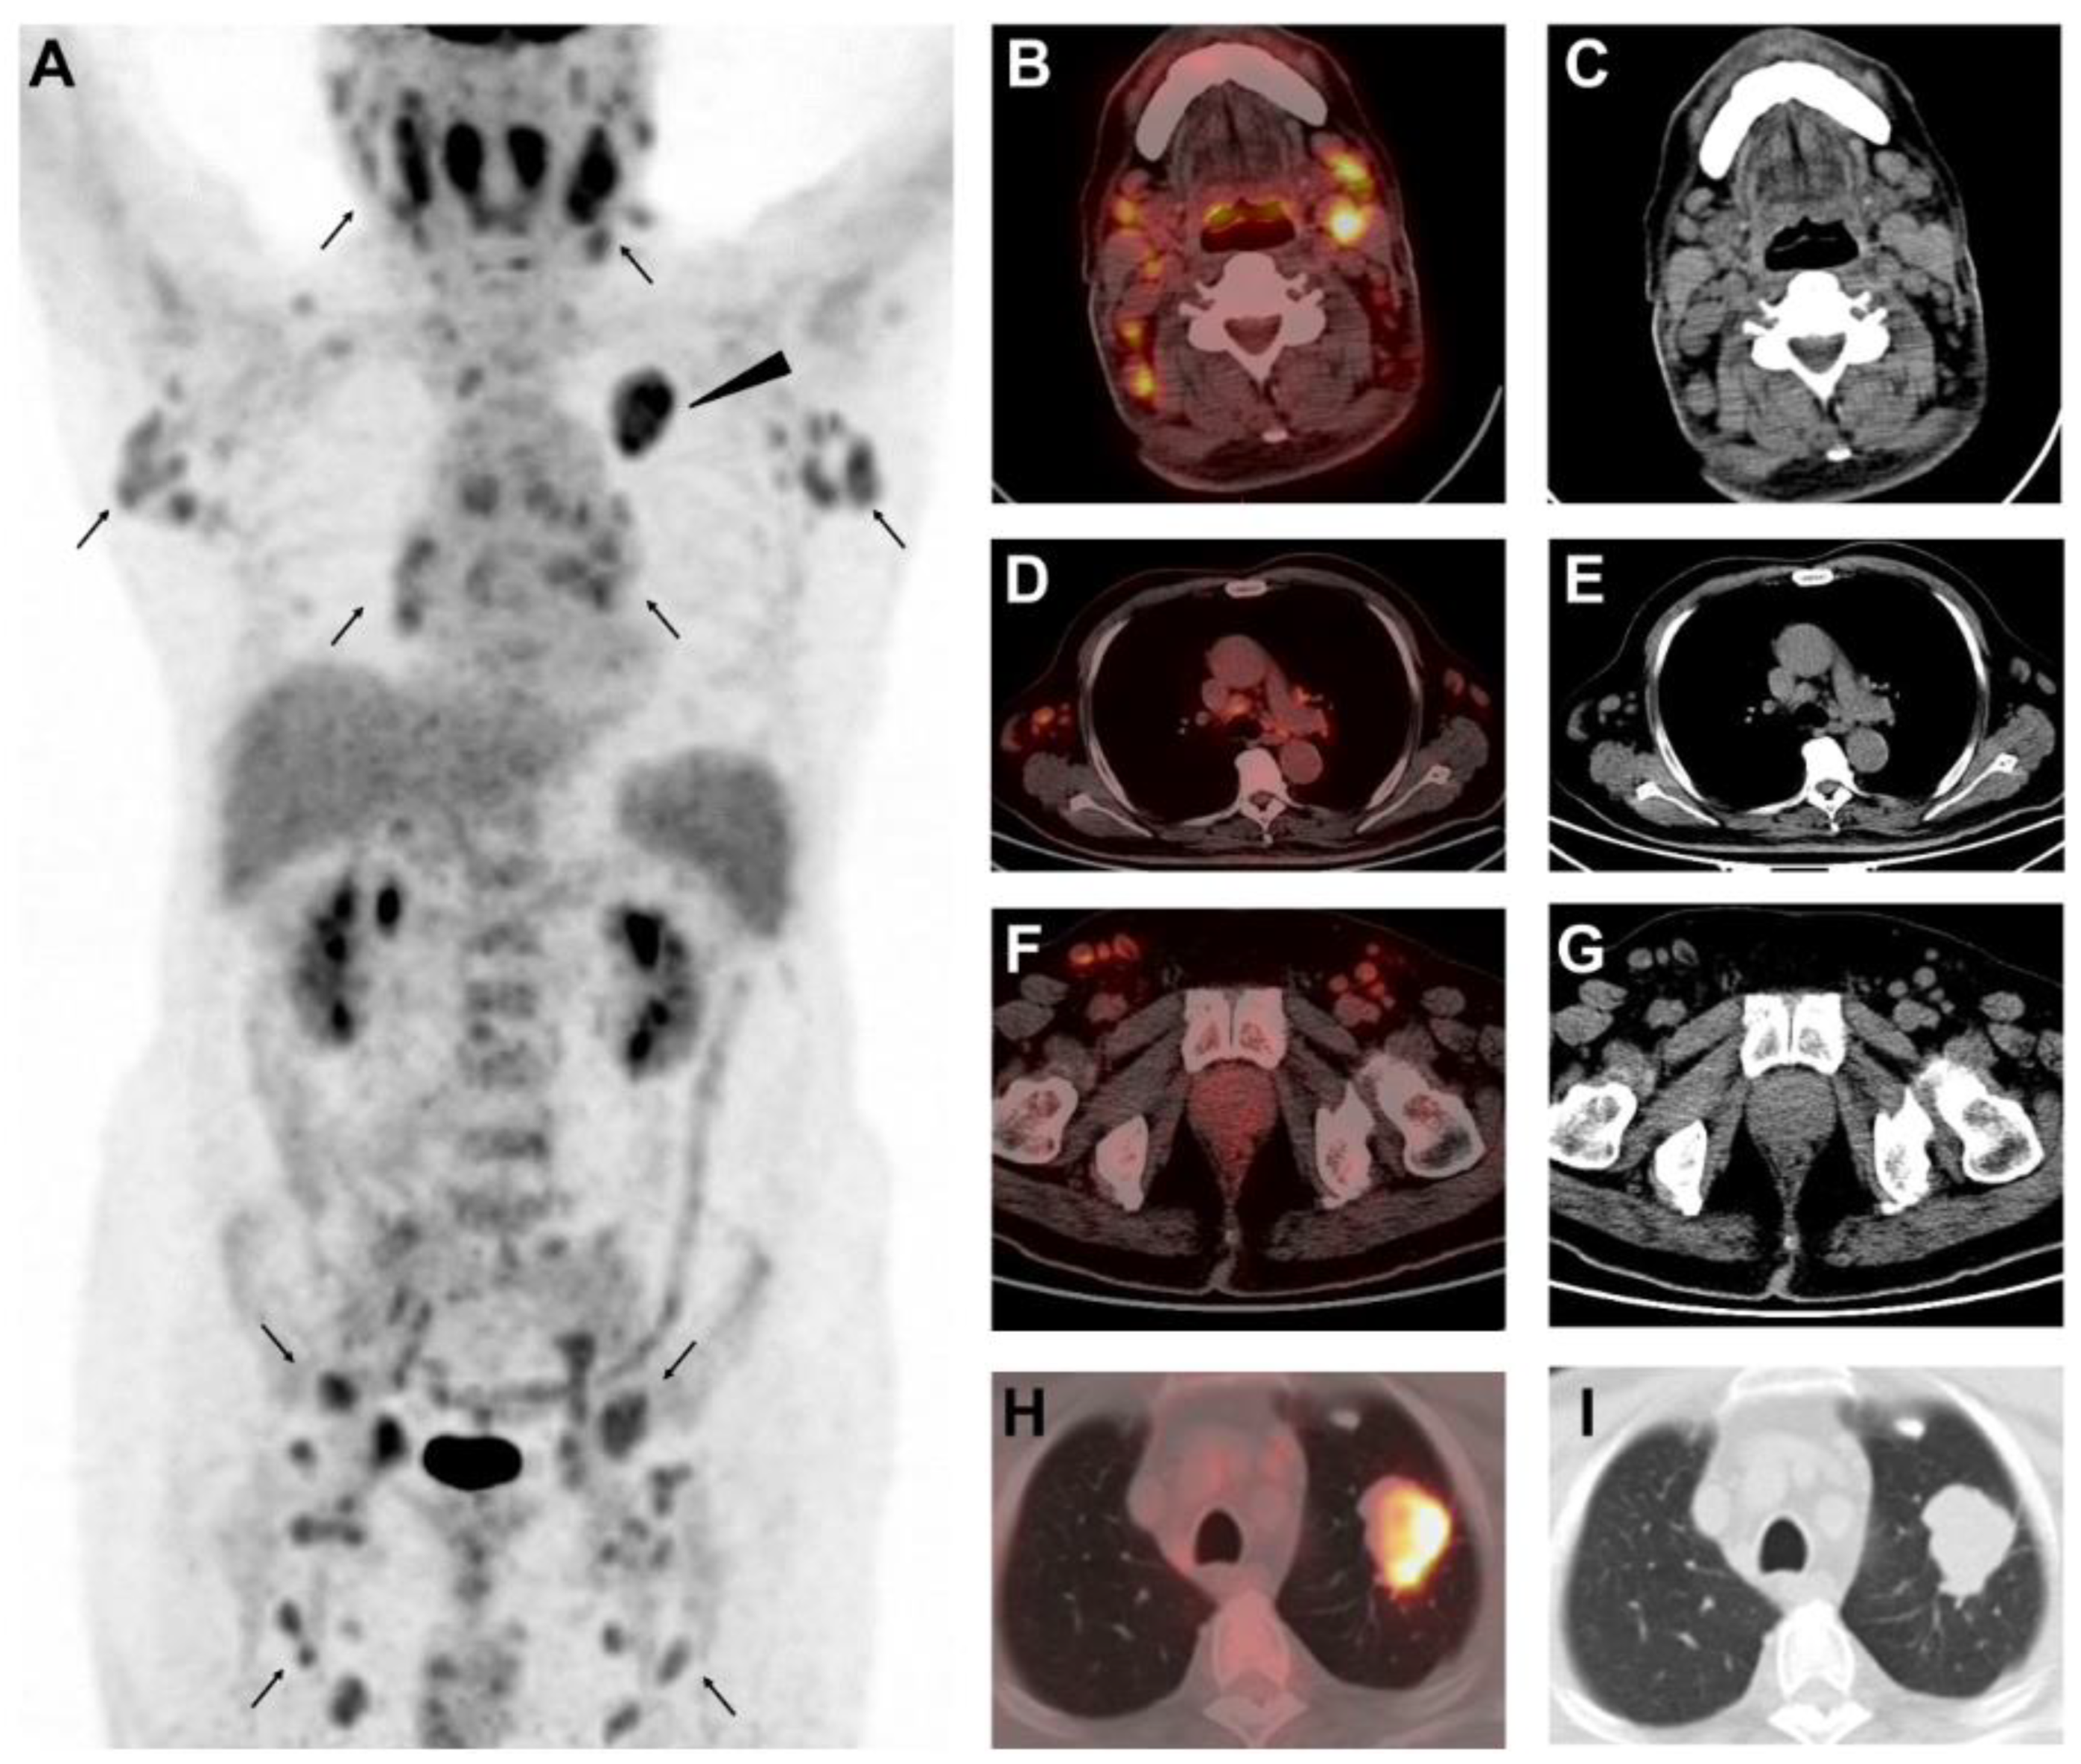

Different Uptake of 68Ga-FAPI and 18F-FDG in Lymphadenopathy Caused by Angioimmunoblastic T-Cell Lymphoma in a Patient with Colon Cancer